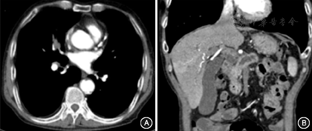

肺癌MIAP临床表现以腹痛(8/8)为主,其次为消瘦(4/8)、恶心呕吐(2/8)、梗阻性黄疸(1/8),背部放射痛(1/8)、皮肤紫癜(1/8)。腹部CT见AP改变(8/8)、胰腺占位(5/8)、腹腔多发肿大淋巴结(4/8)、主胰管扩张(3/8)等。胸部CT示肺部肿块(8/8)、纵膈或肺门淋巴结肿大(7/8)。5例完成腹部超声检查,2例(2/5)未发现明显异常,3例(3/5)发现胰腺低回声病灶。8例患者有5例(5/8)AP原因为胰腺占位,3例(3/8)患者为腹腔淋巴结肿大机械性压迫。图1示某例肺癌MIAP患者CT表现。

注:A示右肺中叶内侧段不规则密度增高影;B示胰腺钩突类圆形低密度影,胆总管胰内段管腔中断,病变以远胰管弥漫扩张,胰腺及胰周渗出性改变